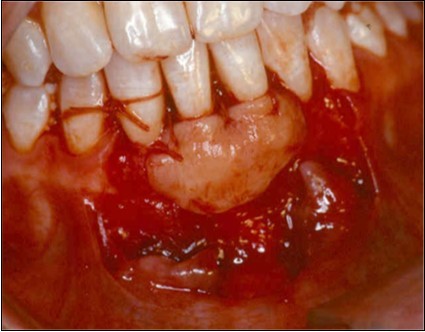

A second surgical site is created on the palate. The length of this is determined by the combines width of the teeth to be covered. The incisions are made in an anterior posterior direction. They are carried to the depth of the palatal mucosa, where they converge just short of the bone. A wedge of tissue is removed as free gingival graft, and its band of epithelium is excised by using Er:YAG laser and acute dissection with scalpel and blade 15C (Figure 4, Figure 4A). The graft is placed in the previously recipient site so that it completely covers the formerly exposed root area (Figure 5). It is then firmly sutured in place with 5-0 gut. The partial thickness, flap is positioned coronally in a manner to cover as much of the graft as possible and sutured in this position to promote maximum adaptation to ensure better healing with less chance of wound dehiscence (Figure 6). The donor site and recipient site is covered with surgical dressing and the patient is instructed in normal postsurgical management. The patient is seen on the 7th postoperative day to remove the surgical dressing and sutures. No additional dressing is necessary, and normal plaque control techniques are resumed (Figure 7)

Figure 4.Donor site area in the palate

Figure 4a.Elimination of the epithelium from free gingival graft by acute dissection